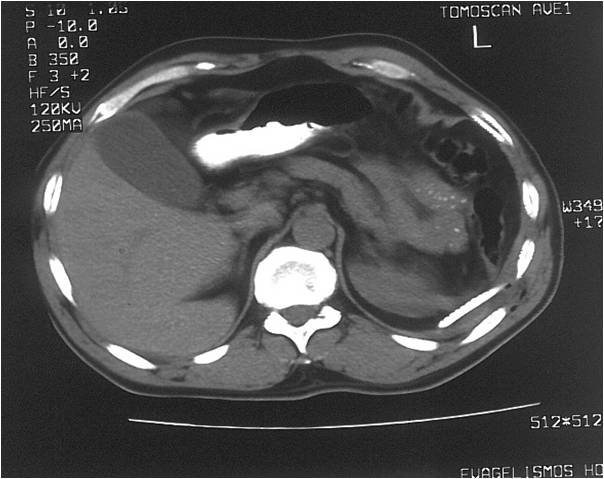

- Abscess post right hemicolectomy

- Successful placement and drainage